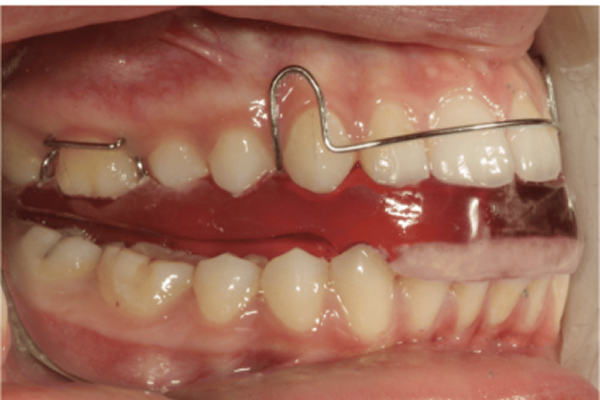

치료방법 : 턱교정(1차교정) 엑티베이터 with 헤드기어

인비절라인 MA : 인비절라인 턱교정장치

엑티베이터 : 전통적으로 많이 사용합니다.

그만큼 효과가 보장되어 있으며, 저는 보통 헤드기어와 병용합니다.

3) 선호하는 장치

2. 엑티베이터+ 헤드기어

제가 선호하는 턱교정장치로,

오랫동안 검증을 받았습니다.

이것으로 턱교정을 하고

2차교정을 진행할 때

인비절라인 퍼스트로 하면

기간의 압박없이 완벽하게

치료할 수 있습니다.